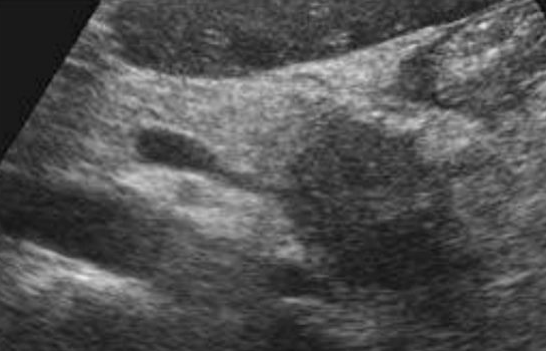

Describe this image

Dx?

A small, hypoechoic, complex mass with microcysts located in the body of the pancreas

Dx: microcystic adenoma of pancreas